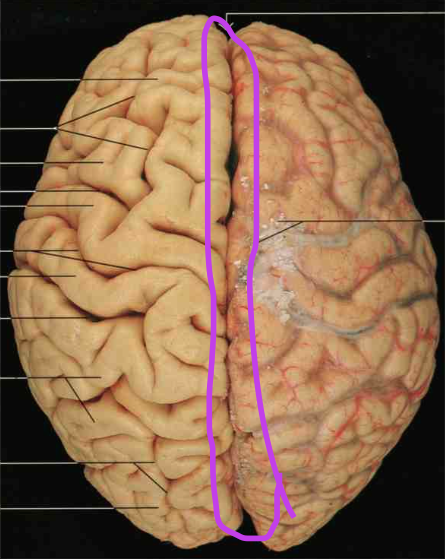

Gyri, sulci and fissures.

In the cerebrum. Gyri are raised ridges, sulci are deep clefts between the ridges and fissures are even deeper clefts between major divisions of the cerebrum.

Frontal Lobe. Section is Cerebrum and diencephalon

Central Sulcus. Section is Cerebrum and diencephalon

Parietal Lobe. Section is Cerebrum and diencephalon

Temporal Lobe. Section is Cerebrum and diencephalon

Occipital Lobe. Section is Cerebrum and diencephalon

Lateral Sulcus (fissure). Section is Cerebrum and diencephalon

Longitudinal Fissure. Section is Cerebrum and diencephalon

Precentral Gyrus. Section is Cerebrum and diencephalon

Postcentral Gyrus. Section is Cerebrum and diencephalon